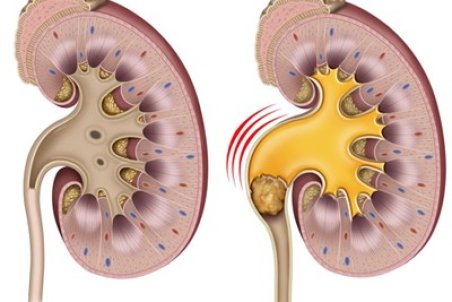

سنگ کلیه جسم سختی است که از موادشیمیایی در ادرار تشکیل شده. انواع متعددی دارد،اما همه دارای علائم مشابهی هستند که می تواند بسیار دردناک باشند،به ویژه اگر سنگ کلیه به مرور زمان رشد کرده باشد.

معمولاً سنگهای کلیه کوچک، بدون بروز علائم و مشکلات خاصی دفع میشوند اما سنگهای بزرگتر در مجاری ادراری لانه میکنند و منجر به درد میشوند؛ اگر این سنگها دفع نشوند، میتوانند عوارضی چون عفونت یا آسیبهای کلیوی را بهدنبال داشته باشند.

متخصصان میگویند سنگ کلیه با فعال کردن رشتههای عصبی باعث بروز درد شدید در بیمار میشود.